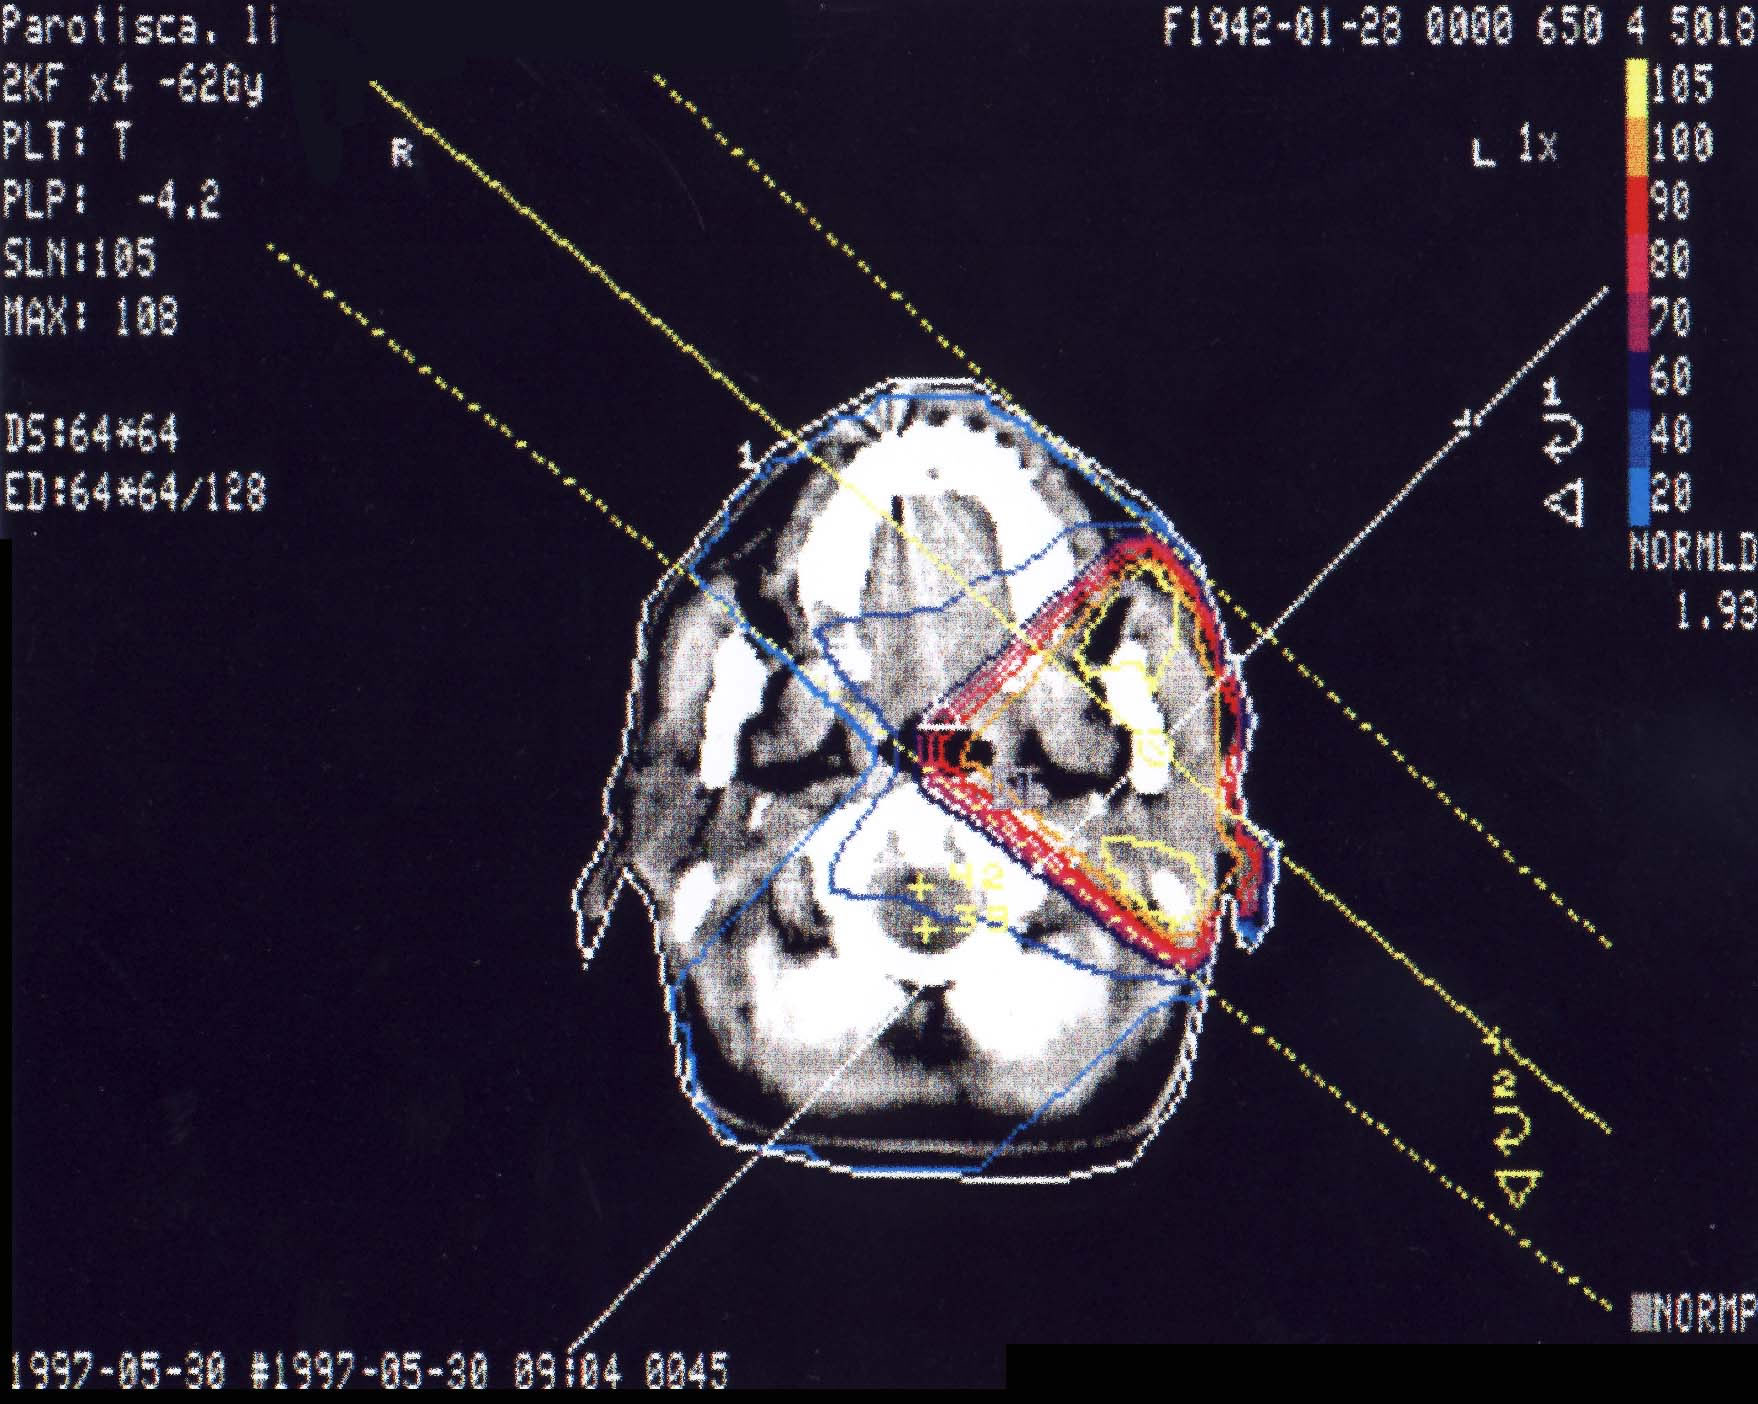

HNO-Karzinome: Bestrahlungsplan

Bestrahlungspläne